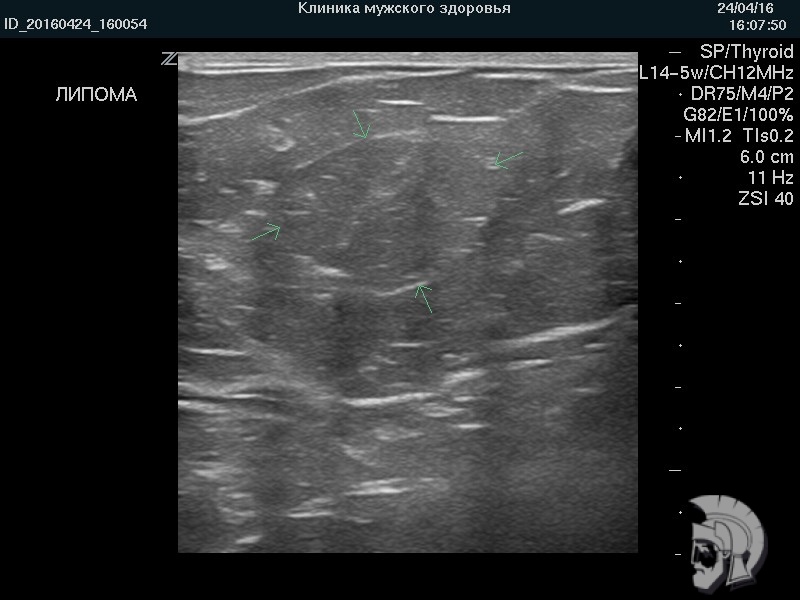

УЗИ груди. Фото липомы у мужчины 23 лет. ЛИПОМА ( «жировик» ) крупного размера представлена образованием тугоэластической консистенции, деформирующим контур груди. Липома указана стрелками |